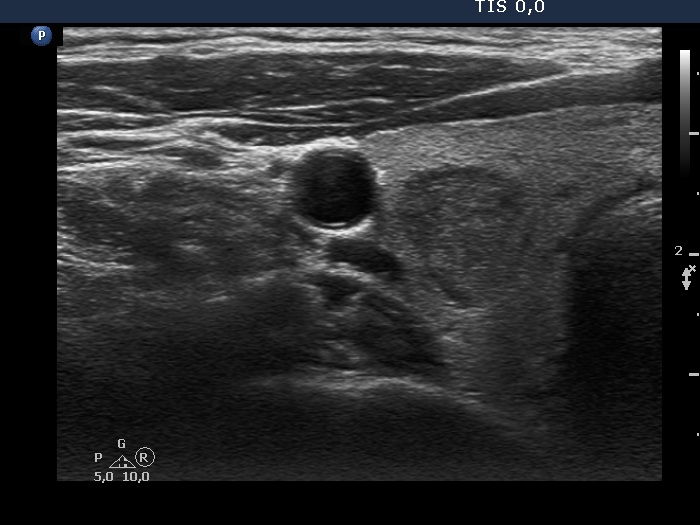

Ultrasonography. The thyroid was echonormal and has tiny hypoechoic areas. The echogenicity index was around 5%. There was a hypoechoic nodule in the right lobe. The lesion showed taller-than-wide shape, had a halo and perinodular vascularity. The dimensions were 12x14x17 mm.